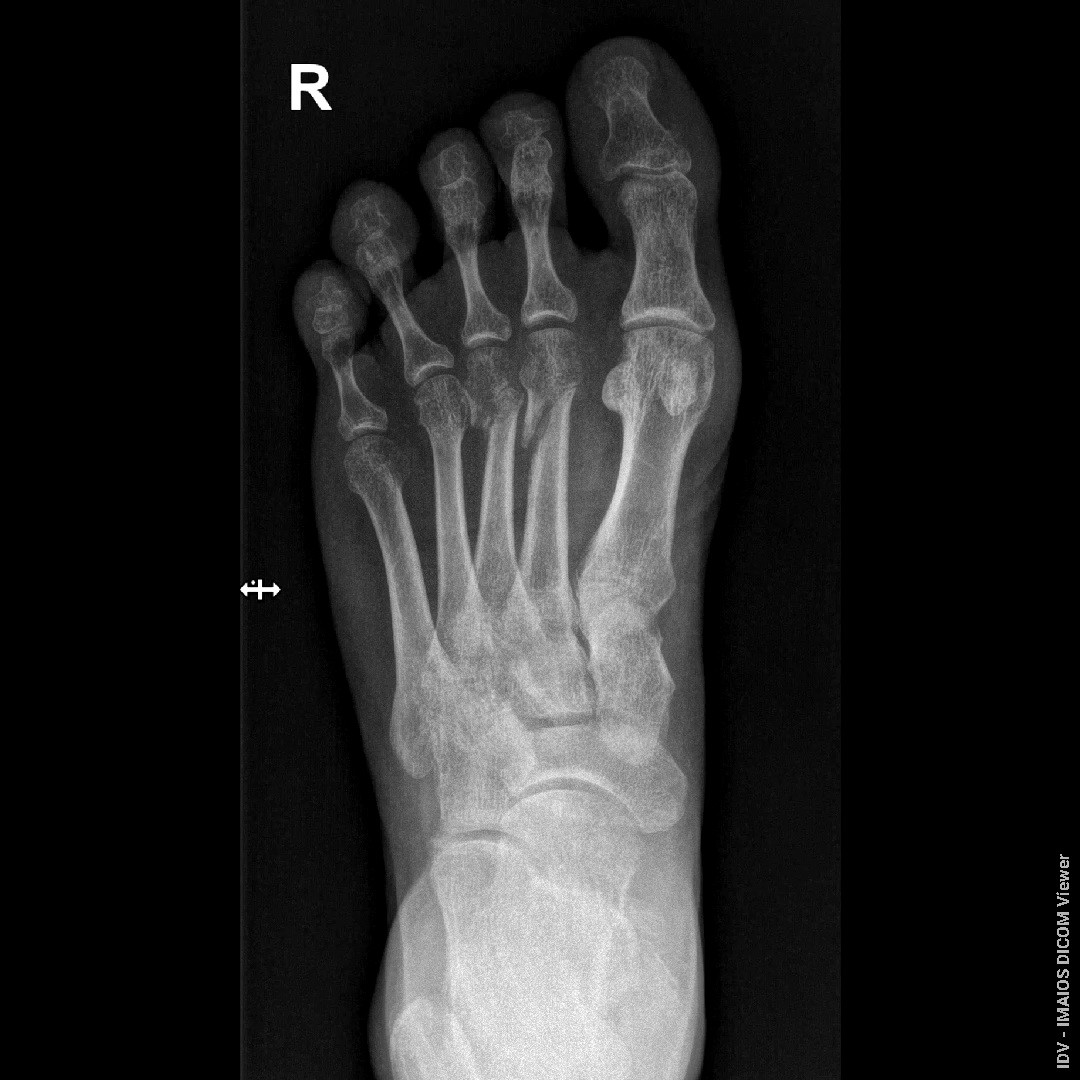

Здравствуйте, доктор, переломы были 23.06.2025, прошло уже почти 7 недель, возможно ли судя по снимкам образования ложных суставов, если будет срастаться плохо? прикрепляю последние снимки от 08.08.2025

Здравствуйте. Ложный сустав за 7 недель не формируется, на снимках есть признаки сращения, но перелом ещё не полностью зажил, поэтому нужен щадящий режим и контроль у травматолога.

Андрей Павлович, Большое Спасибо Вам за ответ! Я понял, что за 7 недель ложнвй сустав не формируется, но если переломы так до конца и не срастутся, возможно ли формирование ложных суставов? На приложеных снимках есть два первичных снимка от 23.06.2025 и один с5имос вчерашний, от 08.08.2025

Да, при отсутствии сращения со временем возможно формирование ложного сустава, поэтому важно наблюдаться у травматолога и контролировать процесс заживления.